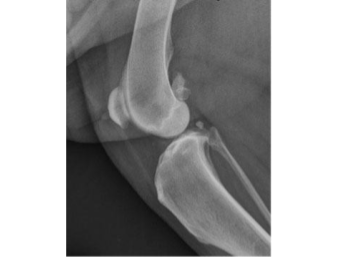

Figure 1. Radiograph of a normal canine stifle (knee joint) with no arthritis.